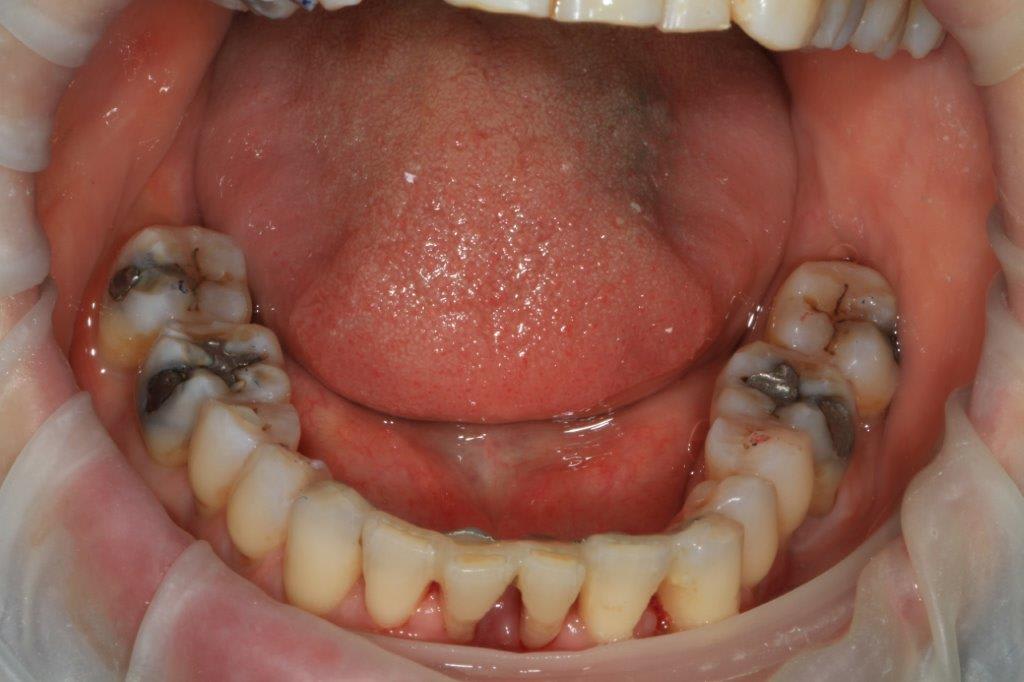

petit boulot de ce jour, "coronoplastie de sauvage", afin d'essayer de supprimer les contacts nocifs... ensuite endo 24/25/26.

en occlusion, ça parait moins destructeur, la suite mardi prochain.

surtout dans des cas comme celui là où il y a des mylolyses bilatérales et une double occlusion.

Sur une occlusion qui ést du genre un coup a gauche , un coup a droite, son calage était au départ sur le secteur incisif.

Elle se servait du bloc ant comme un point d appuis pour se faire sa translation postérieure.

Le fait de ne pas supprimer les décalages de crête, alors que tu lui a enlevé son calage ant , et va faire du bruxisme centré ( serrage ') de compensation sur les crêtes les plus saillantes n ayant plus d engrenement suffisamment stable .

Bref on voit mieux sur ces photos que ce sera le haut qu il faudra couronner en fonction du bas qui lui n'est pas dégueulasse .